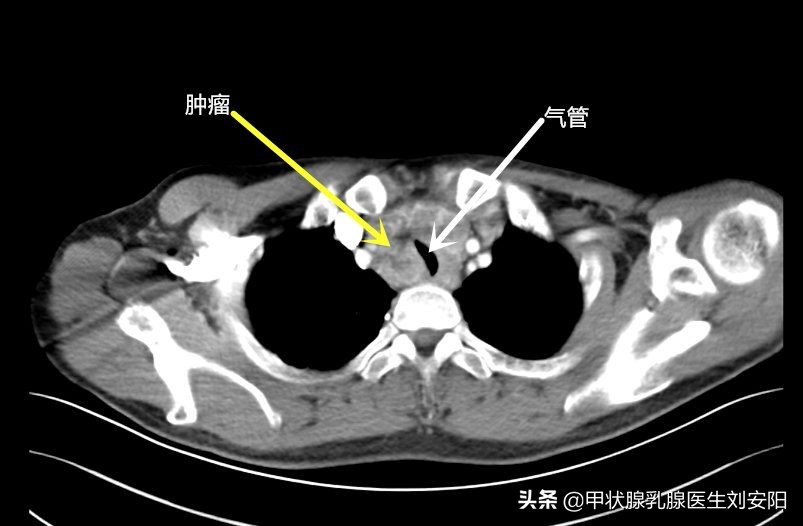

近日病房收治一名青年男性,确诊为甲状腺髓样癌,诊断时肿瘤已经侵犯气管,造成气管受压(CT见下图),憋气,此时手术比较困难。为什么没有早点发现呢?在询问病史的过程中,病人主诉反复腹泻已有一年余,当地医院做了大量关于消化道的检查,没有发现任何问题,等出现了呼吸困难时才开始注意胸部及甲状腺,行颈胸部CT发现肿物并诊断为甲状腺髓样癌,若在一年前发现,治疗会相对容易一些,治疗效果也会好。那么究竟什么是甲状腺髓样癌,为什么会导致腹泻,如何早期发现、早期治疗呢?